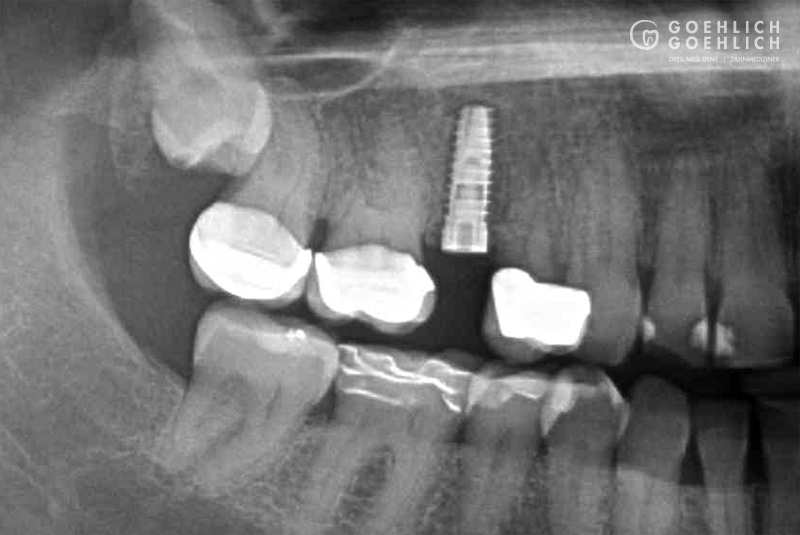

Mittels digitaler Volumentomographie (DVT) sind wir in der Lage, die knöcherne Ausgangslage vor Implantation dreidimensional darzustellen. So können die genauen Lagebeziehungen zu Nerven oder auch zur Kieferhöhle optimal bestimmt werden.

Implantate bestehen aus dem körperverträglichen und langlebigen Metall Titan. In einem minimalinvasiven operativen Eingriff setzen wir das Implantat in den Knochen ein. Die speziell bearbeitete Oberfläche garantiert ein zügiges Einheilen und das feste Verwachsen mit dem umgebenden Knochengewebe. Implantate können darüber hinaus den gefürchteten Knochenschwund in zahnlosen Kieferabschnitten verhindern oder verzögern. Den eigenen Zahnwurzeln ähnlich, übertragen Implantate die Kaukräfte auf den Kieferknochen. Dieser Trainingseffekt ist ein wichtiger Reiz für den Erhalt des Knochen- und Stützgewebes. Deshalb sollten Implantate möglichst bald nach dem Verlust oder Entfernen eines Zahns verankert werden.